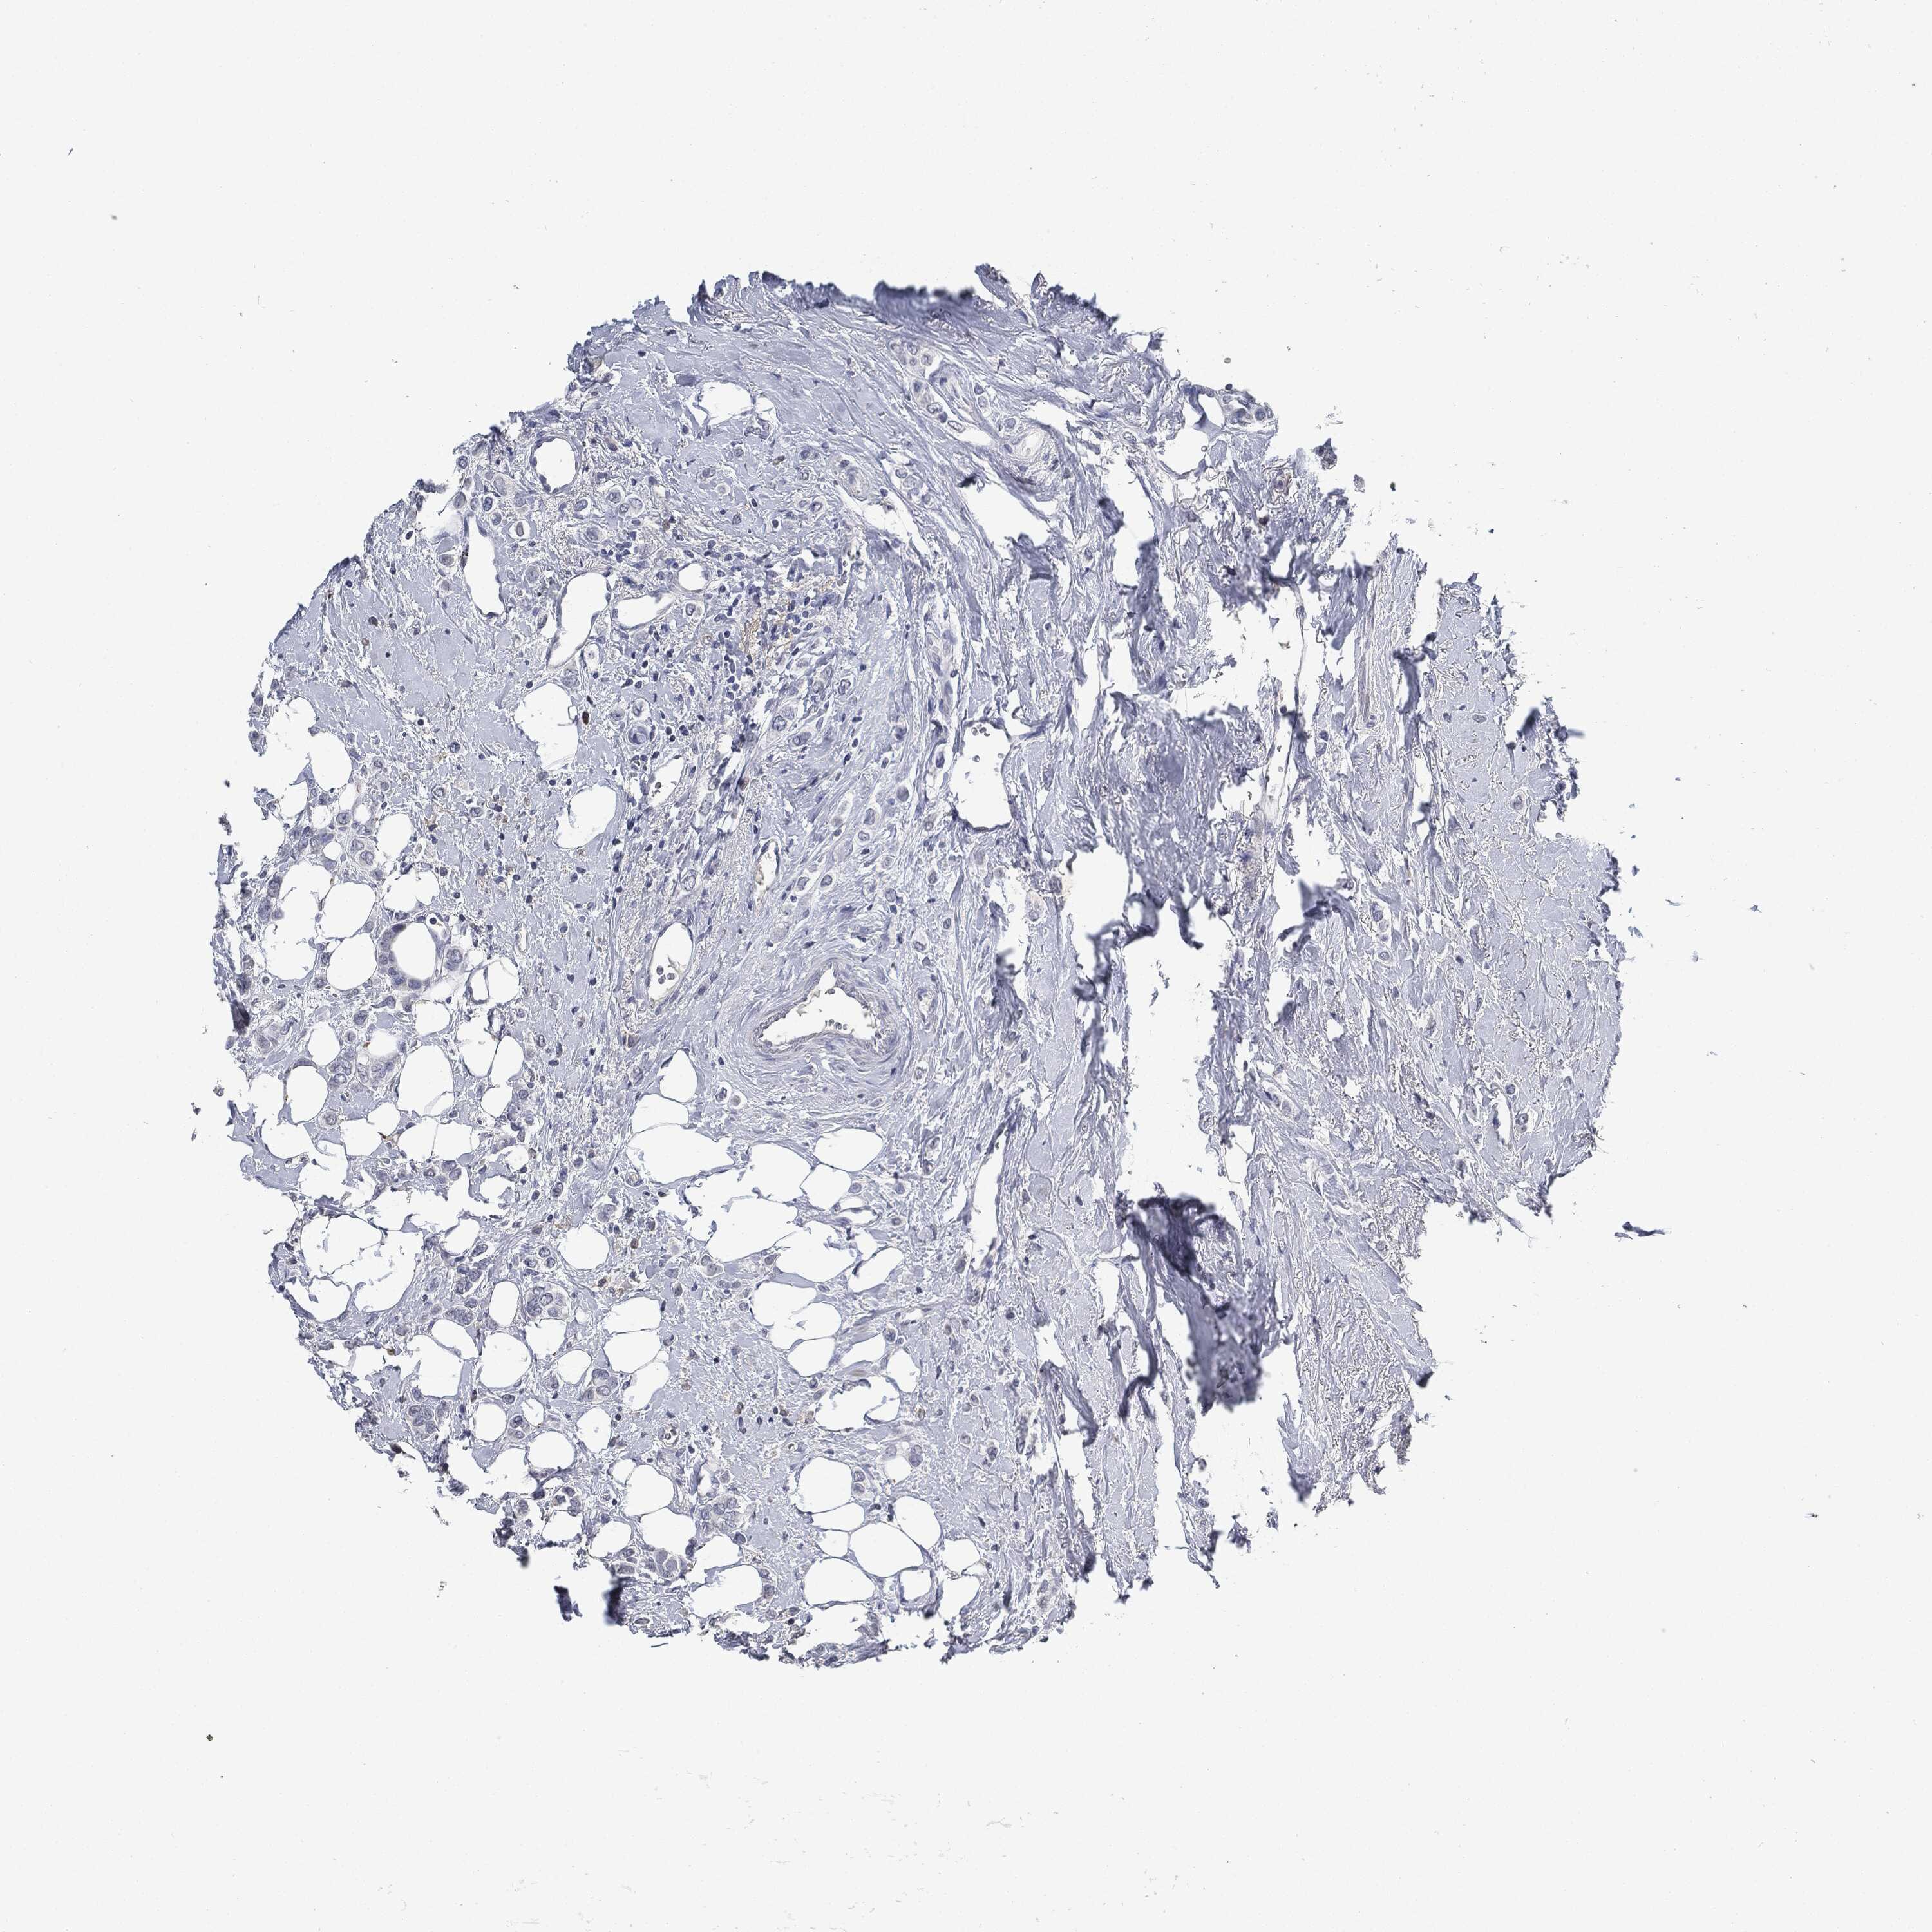

BRCA TCGA BRCA VALIDATION PROTEIN EXPRESSION

ANTIBODIES

AND

VALIDATION